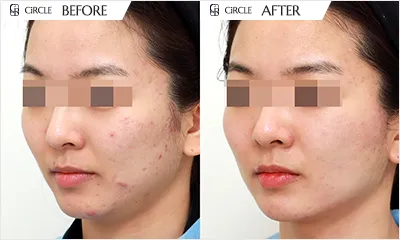

Cystic

Comedonal

Nodular

Papular

Pustular

Scars